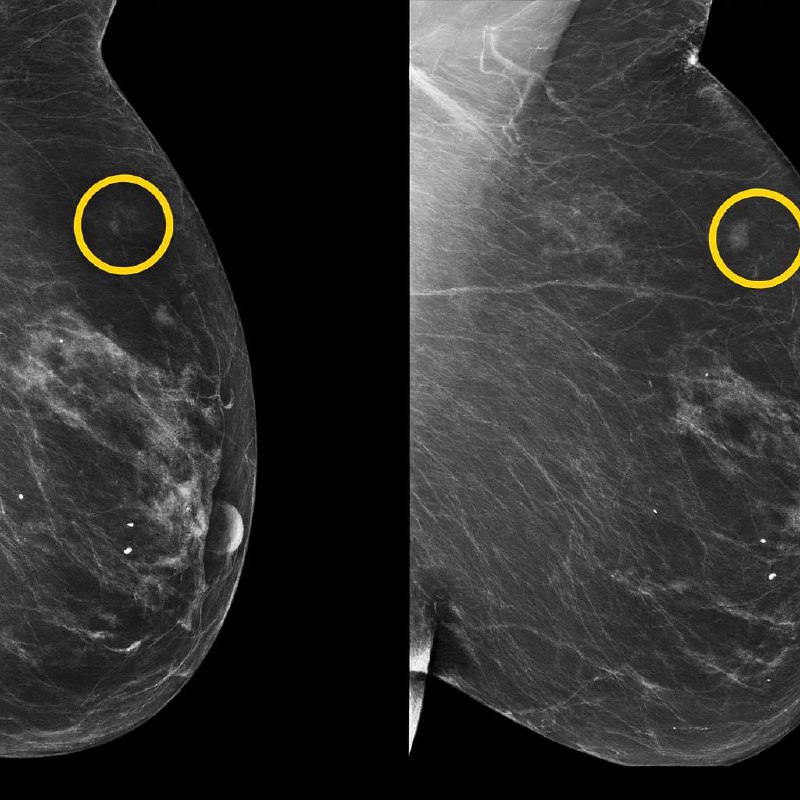

Aujourd’hui, la mammographie détecte ce qui est déjà là.

L’intelligence artificielle, elle, peut repérer ce qui est en train de naître dans l’ombre — des nuances infimes dans les tissus, des micro-indices trop subtils pour l’œil humain, même expérimenté.

Que la mammographie ne soit plus seulement une image,

mais un texte codé que l’algorithme sait lire comme un linguiste lisant un manuscrit ancien.

comment pouvions-nous vivre dans un monde où nous ne voyions que l’évident et manquions ce qui se cachait entre les pixels ?